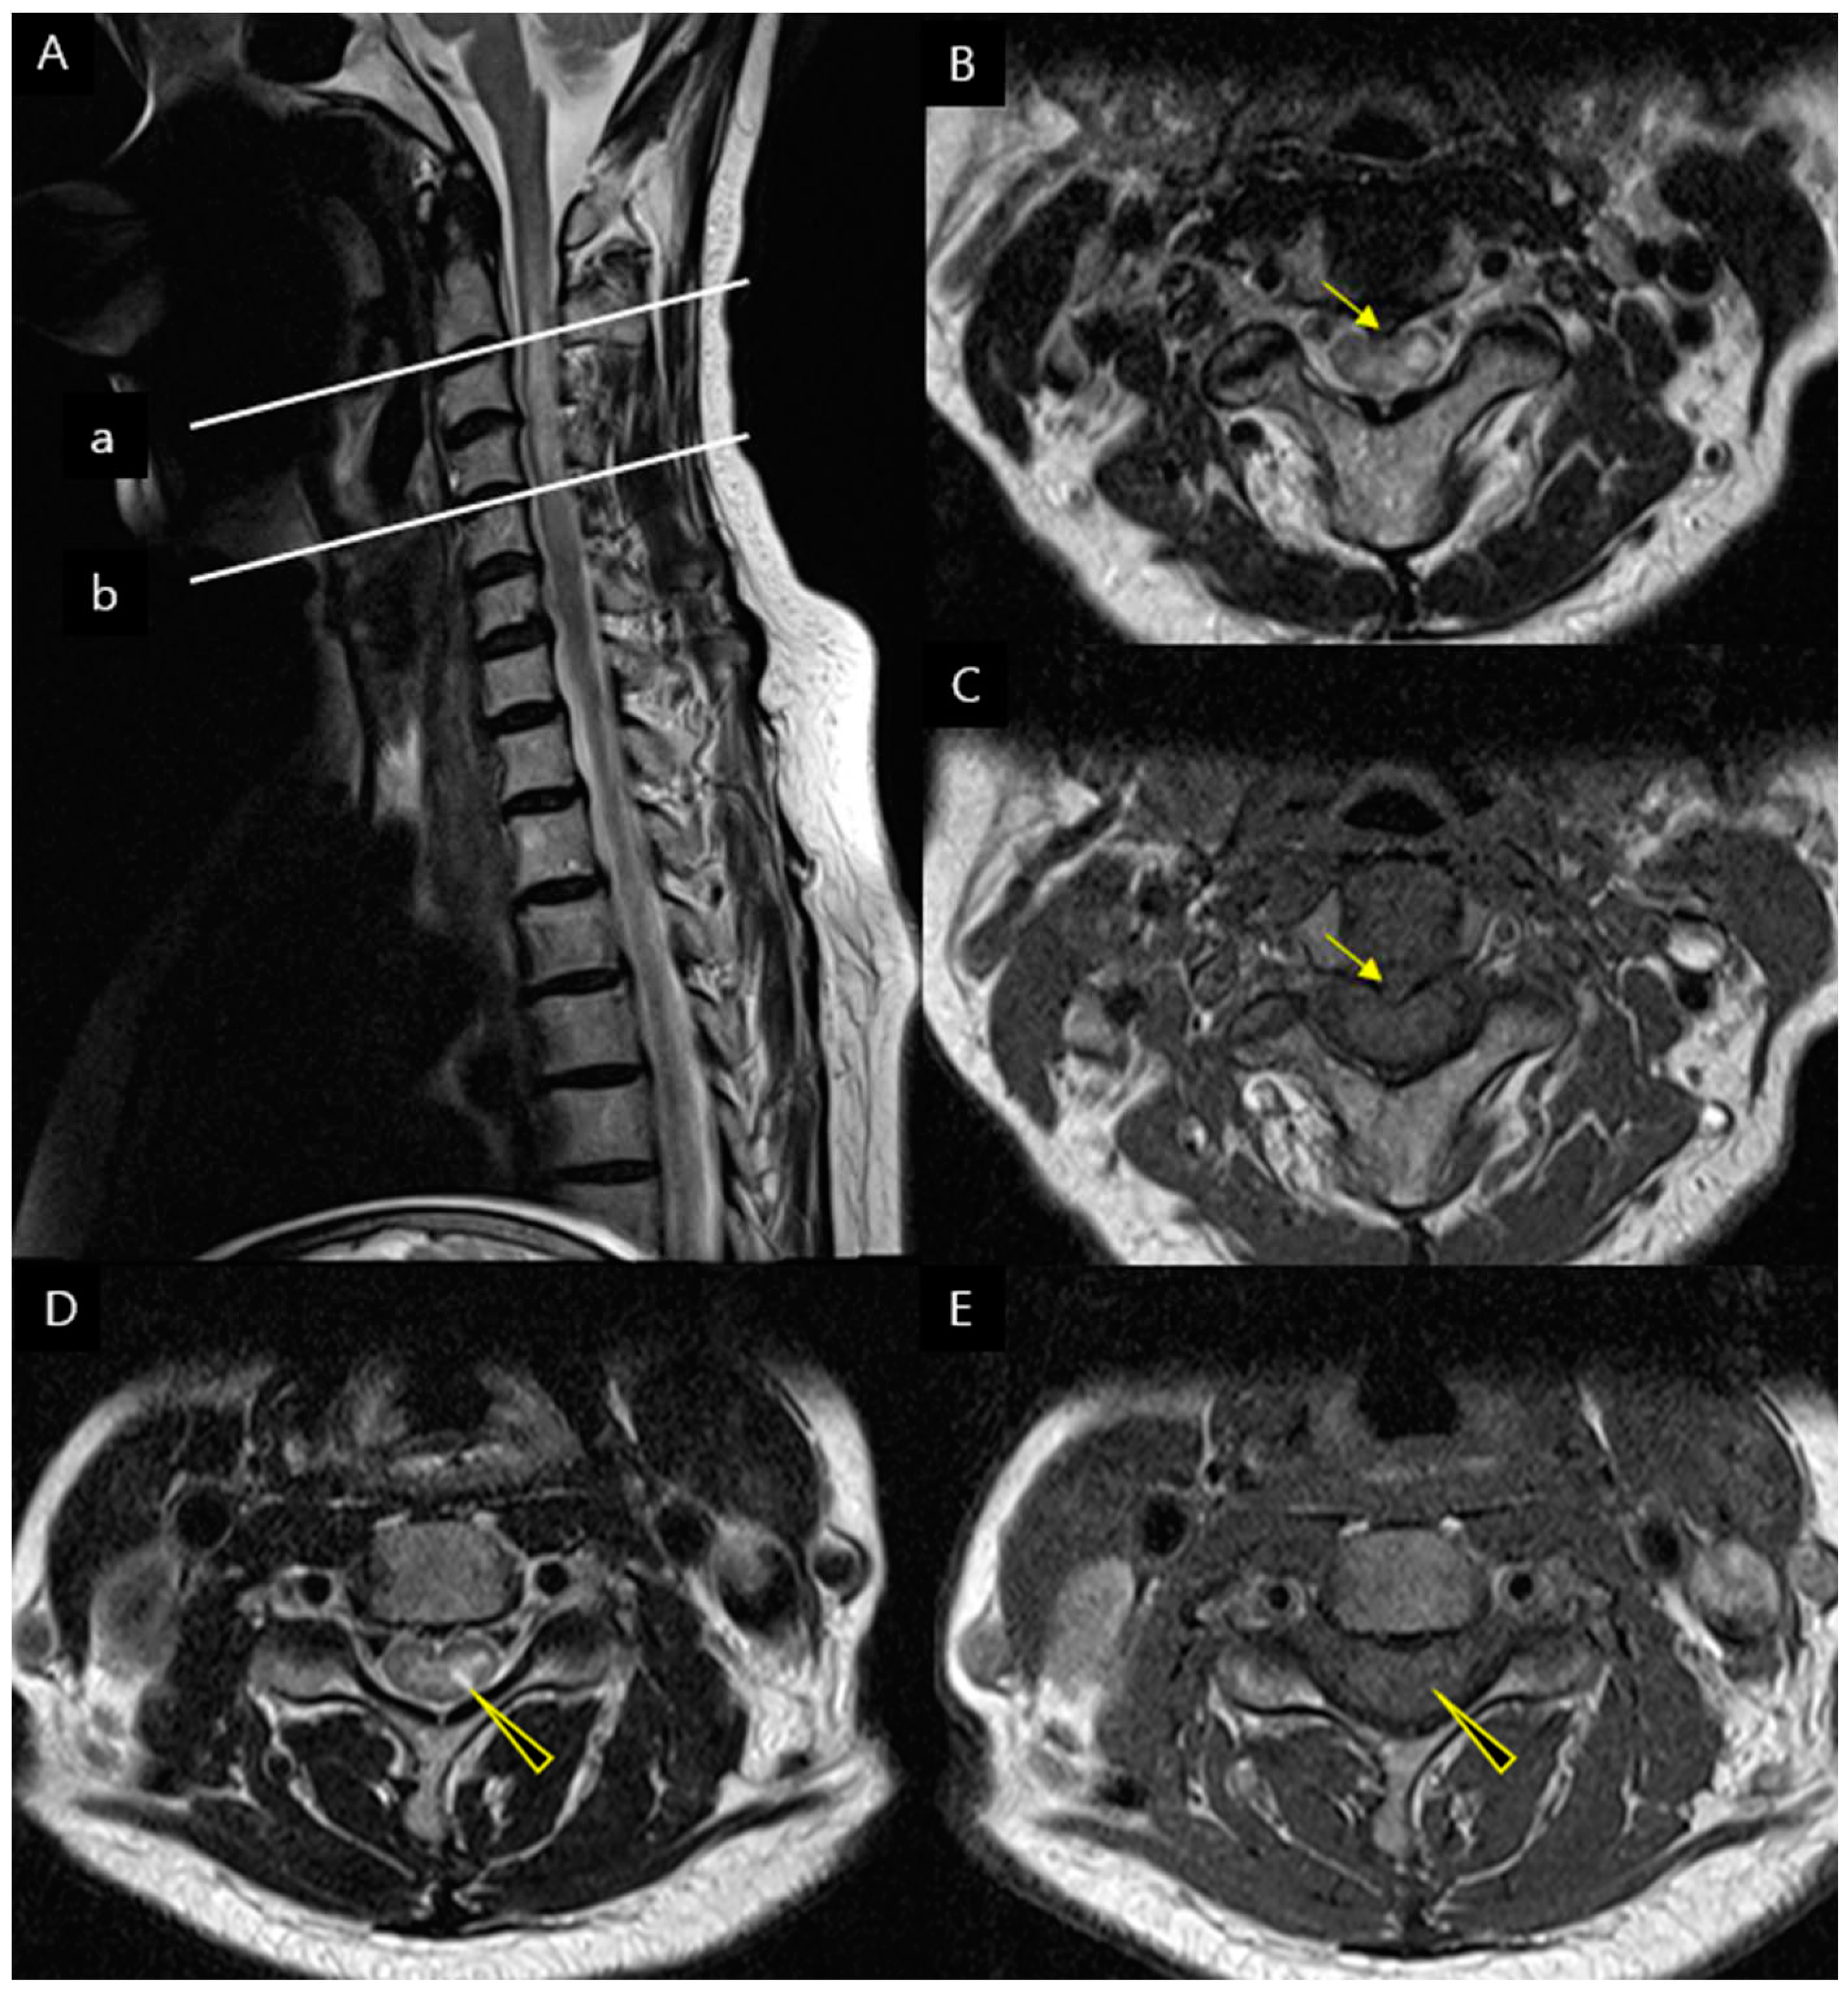

Three years after the initial diagnosis of CSM, the patient presented to the hospital three days ago with sudden onset of left upper extremity motor weakness and mild gait disturbance. On the physical examination, the patient displayed varying degrees of motor weakness on the left side, as assessed by MMT: shoulder flexion scored 2, elbow flexion scored 4, wrist extension scored 4, finger flexion scored 4, finger extension scored 3, hip flexion scored 4, knee extension scored 4, and ankle dorsiflexion scored 4. Sensation to touch and pinprick was normal. The knee-jerk reflex was relatively within the normal range. Hoffmann's sign exhibited equivocality on the left side, while Babinski reflexes and ankle clonus were absent. In addition, the patient reported nonradiating pain with a NRS score of 3, which was accompanied throughout the left upper limb. The cervical spine MRI showed findings consistent with longitudinally extensive transverse myelitis (LETM). In the sagittal view, there was evidence of longitudinally extensive high signal at the C1 to C5. In the axial view, features indicative of transverse myelitis were observed, supporting the diagnosis of LETM. (Figure 2)

Figure 2. Spine magnetic resonance imaging findings on second hospitalization. On follow-up cervical MRI, it was observed that there was more extensive involvement with enhancement compared to the initial MRI performed during the patient's first visit. (A) T2-weighted sagittal image reveals increased signal intensity of spinal cord at the C1 to C5 levels. (B) T1-wegihted sagittal view revealed dorsal enhancement with Gadolinium contrast extending 3 vertebral segments. (C) The T2-weighted axial image reveals hyperintense lesion at the C2-3 level, indicating the presence of bright spotty lesions (BLSs) (yellow arrows) (D) T1-weighted image reveals partially hypointense or isointense (yellow arrows).